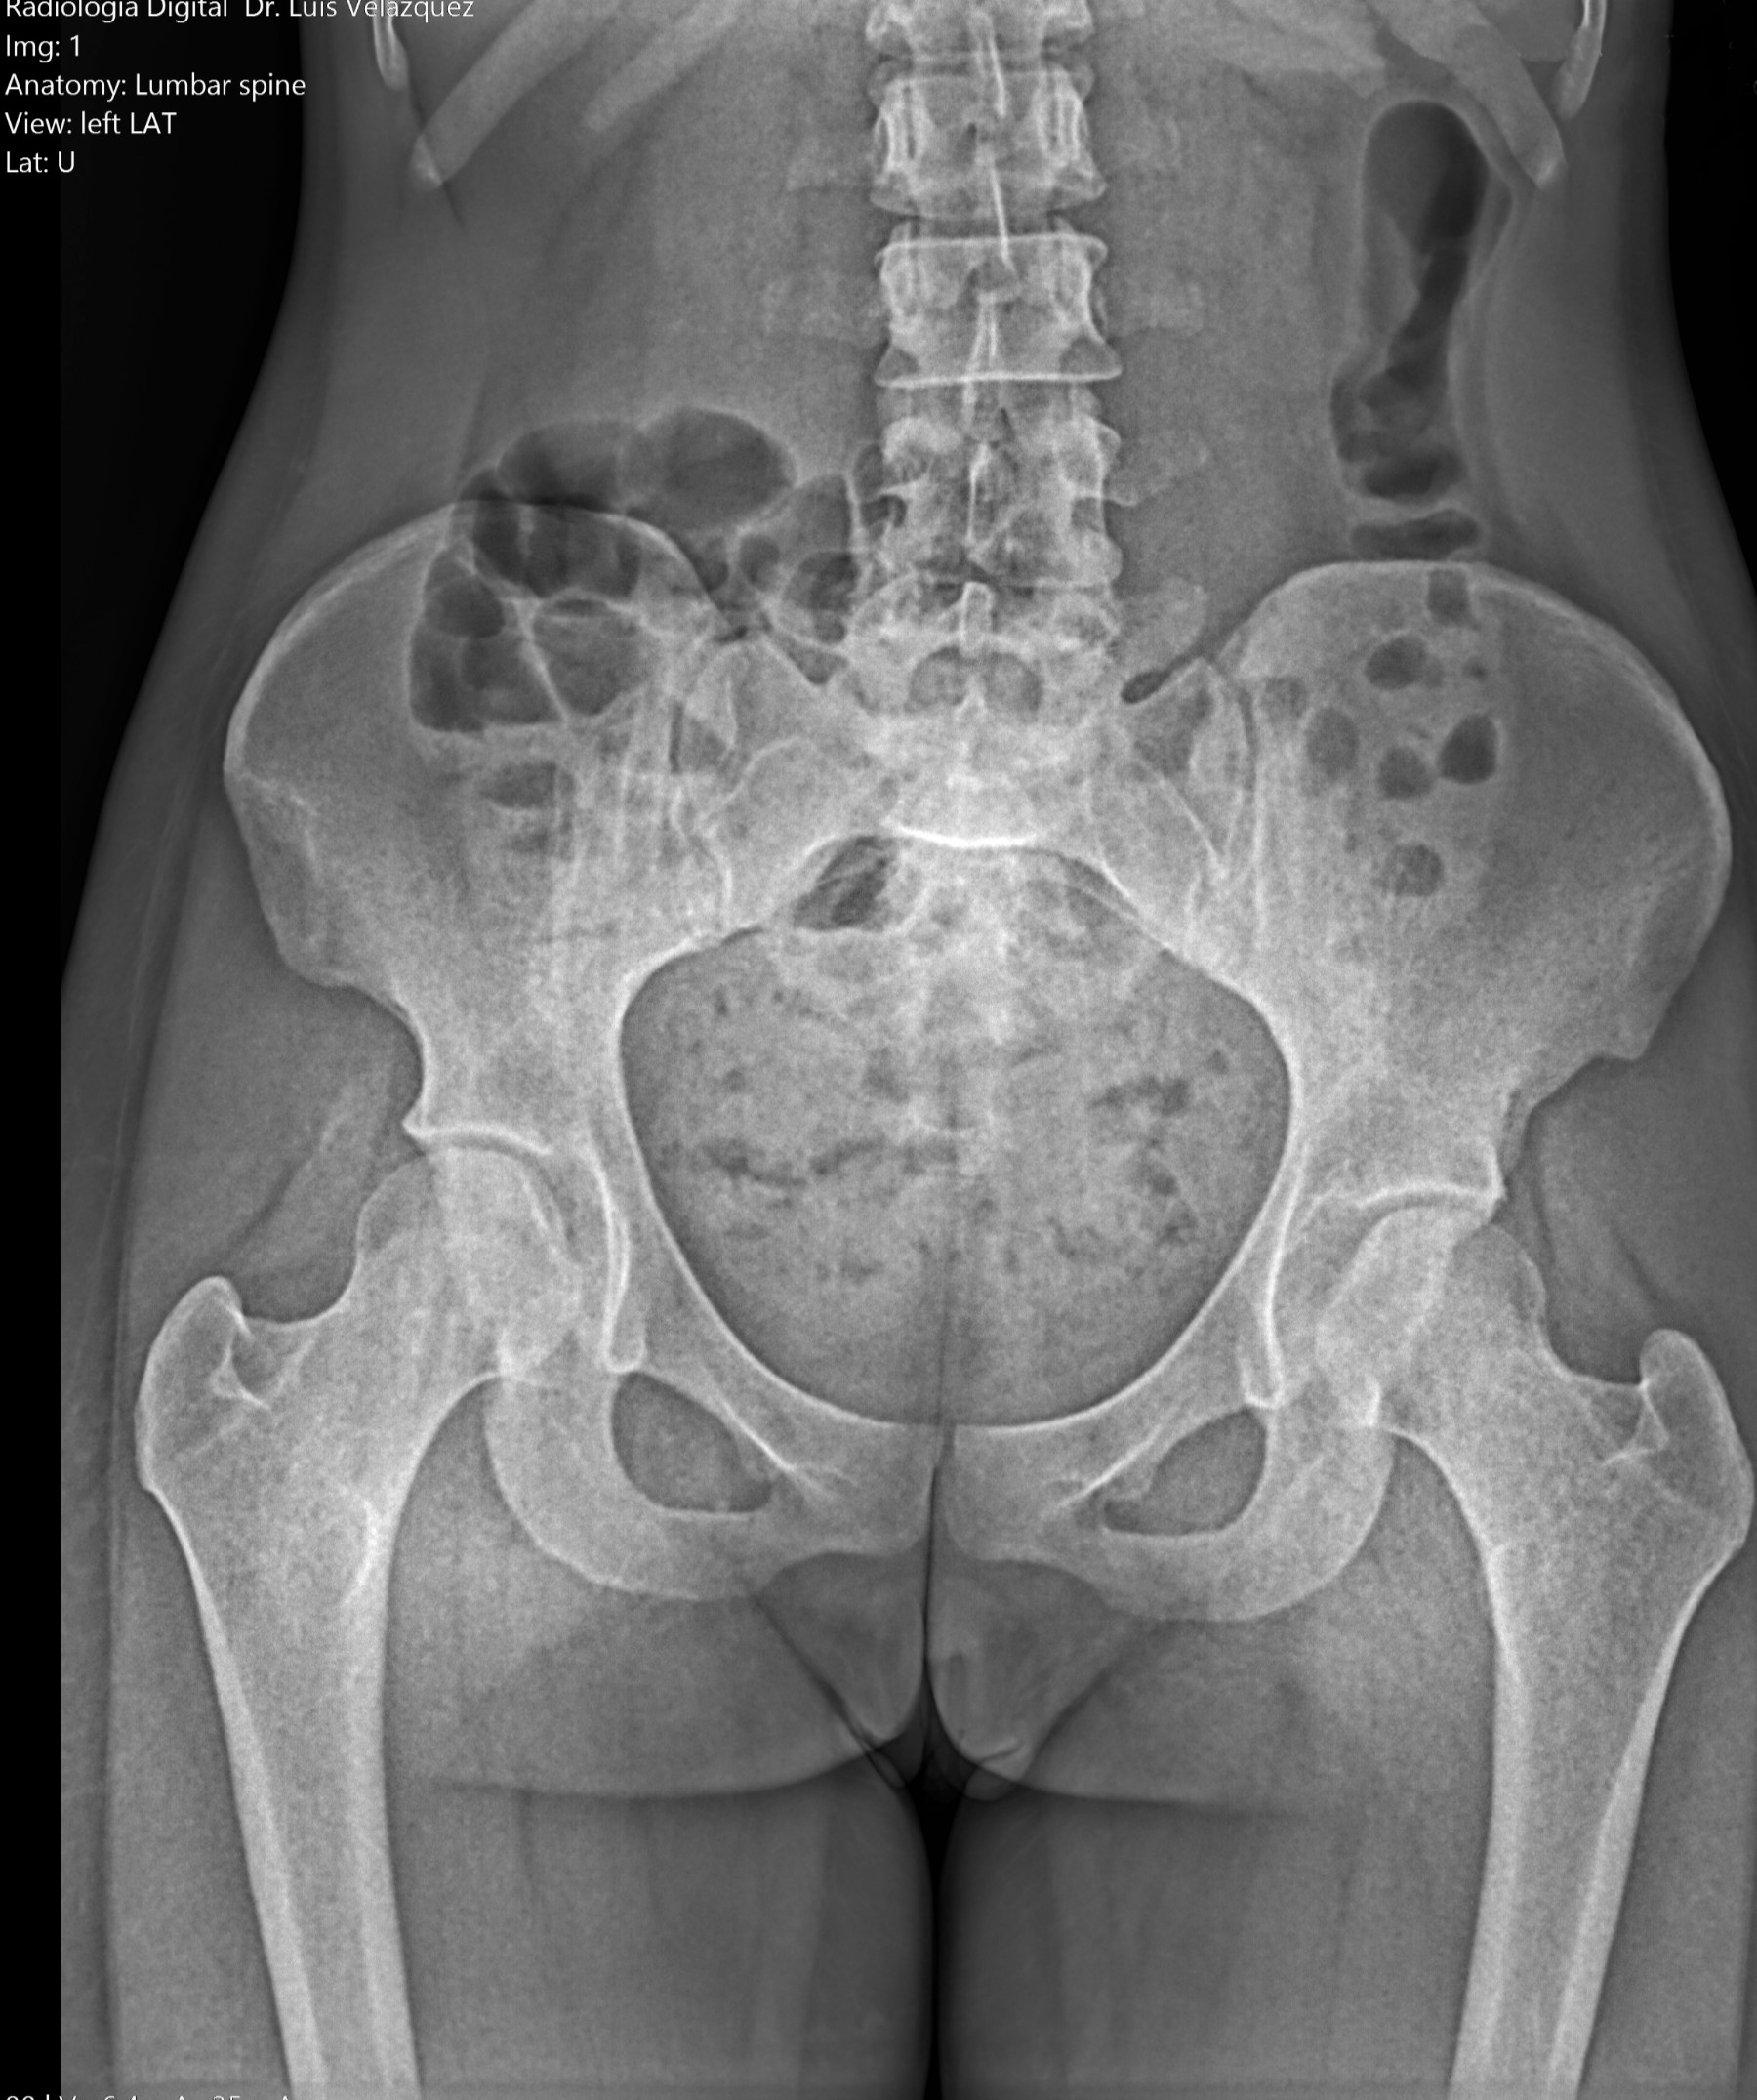

Desde el descubrimiento de los rayos “X” y las placas radiográficas por Wilhelm Conrad Roentgen y su posterior difusión a través de la Asociación Físico médica de Wurzburg el 28 de diciembre de 1895, que fue la primera asociación que habló de los nuevos rayos que podían penetrar el cuerpo y fotografiar los huesos, ha habido muchos cambios tanto en la forma de obtener, procesar e incluso en la forma de visualizar, manejar y almacenar las placas radiográficas.